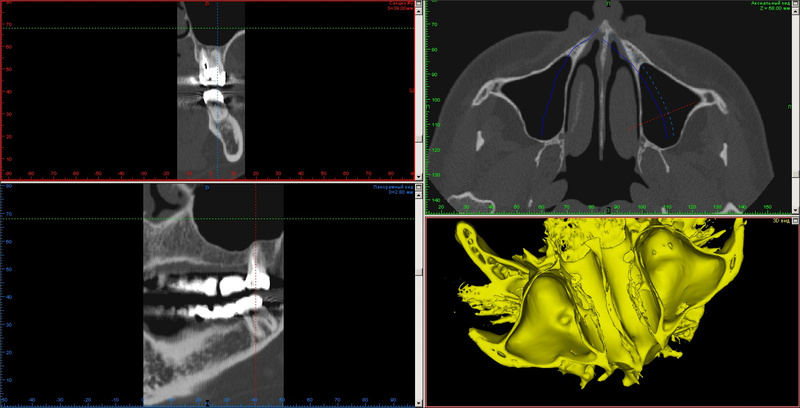

1. Кому верить - рентгенологу, который сказал, что кисты могут быть в других местах и надо КТ, или ЛОРу, которая сказала расслабиться и выдыхать? Мне в принципе не жалко, но я за последнее время делала несколько рентгенов (колено, шея в динамике, ОПТГ), лишний раз "дозу" получать без необходимости не хочется.

2. Стоит ли вообще паниковать? Т.е. может ли быть обнаруженная на снимке ОПТГ киста вовсе не ею, а чем-то другим, злокачественным? Пару лет назад я также делала ОПТГ, никаких кист мне не диагностировали (не было? или не заметили?).

В целом меня пока (ттт) ничего не бесопокит, каких-то особенных симптомов нет, гайморитами ни разу не страдала, насморк не чаще и не тяжелее чем у всех проходит, т.е. если бы не этот снимок, я бы даже и не узнала ничего.